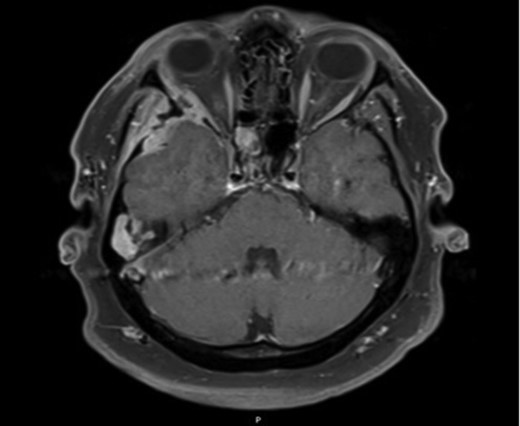

Axial MRI image demonstrating ocular involvement, with abutment of right lateral rectus muscle, as well as enhancement of temporal lobe.

Due to the extensive nature of the findings, a magnetic resonance imaging (MRI) scan of the head was undertaken and demonstrated bony erosion of the lateral wall of the right orbit, right superior rectus muscle abutment and minimal involvement of the antero-inferior surface of the temporal lobe. The appearances were suggestive of fibrous dysplasia, chronic inflammatory/infective pathology or less likely metastatic carcinoma.